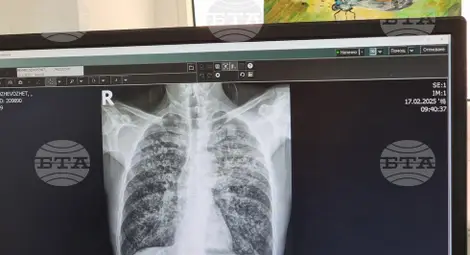

Туберкулозата е тежко инфекциозно заболяване, което засяга най-често белите дробове, но също така и други органи на човешкото тяло, като се смята, че около една четвърт от хората в света са носители на микробактерии, причиняващи туберкулоза (латентна туберкулоза). Тези хора са асимптоматични и не са заразни за околните, но средно около 10% от тях развиват активна туберкулоза.

Симптомите на белодробната туберкулоза са кашлица с храчки (понякога с кръв), болка в гърдите, задух и общо усещане за слабост. Извънбелодробната туберкулоза може да засегне всяка част на тялото, като най-честата локализация са ставите и костите.